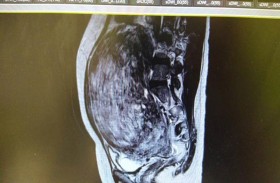

استئصال ورم ليفي بحجم كرة القدة بالمستشفي السعودي الالماني دبي

أجرى فريق الجراحة النسائية في المستشفى السعودي الألماني دبي عملية ناجحة لاستئصال ورم ليفي رحمي ضخم بالجراحة التنظيرية،  وكانت المريضة قد راجعت المشفى بشكوى انتفاخ في البطن وصعوبة في التنفس، و بعد ... إقرأ المزيد